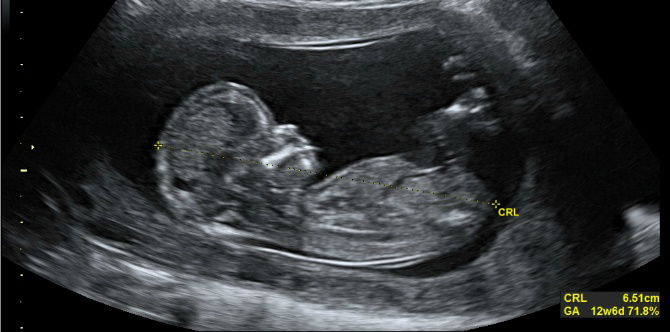

In a very rare and amazing moment, an MRI image shows the legs of the developing fetus poking outside the mother's uterus.

One look at the image below, and you might think that the baby kicked it’s feet right out of the mother’s uterus. In reality, it’s because of a tear in the woman’s uterus which caused part of the amniotic sac to pop out.

While the image might look alarming, the woman actually had no idea of what was happening inside her body. Only when she went in for a routine ultrasound was the problem identified.

According to Dr. Pierre-Emmanuel Bouet, an OB/GYN at the Angers University Hospital in France, the condition is “extremely rare”, and it’s one of only 26 reported cases worldwide.

Based on the report by Dr. Bouet’s team, it’s the woman’s 6th pregnancy, and her 5 previous children were all delivered through C-section. It could be possible that the C-sections have weakened the walls of her uterus. He added that while the C-section scars were strong, the area surrounding it was fragile, and the forces that were exerted during the woman’s pregnancy could have caused the tear.

The woman’s doctors informed her and her husband regarding the risks, which include uterine tearing, preterm birth, and placenta accreta, or wherein the placenta fails to detach from the walls of the uterus after giving birth.

Bouet added that the amniotic sac can also rupture. In case this happens, doctors can perform an emergency C-section to try and save the baby. However, if it’s still too early in the pregnancy, the chances of survival can be very slim.

According to the report, the woman and her husband chose to go through with the pregnancy, whilst being closely being monitored by doctors.

By 30 weeks, the tear was so large that part of the baby’s abdomen also went outside of the uterus. Thankfully, the baby had successfully been delivered through C-section, weighing 3 lbs at the time of delivery. The doctors checked in with the mother and her son after six months, and they have noted that both of them are doing well.

Check out the amazing photo below:

Photo from: Twitter.com / Live Science